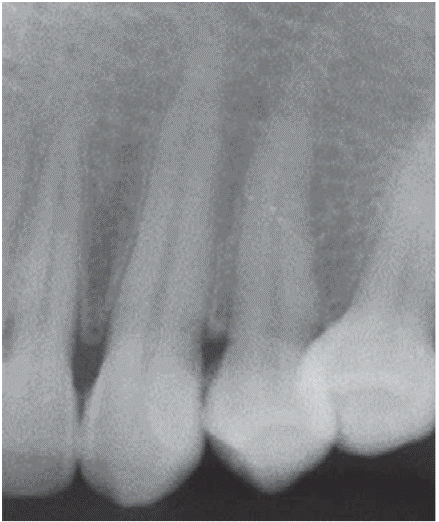

Al examen radiográfico se observó alteración de la cresta ósea entre las piezas 1.1 y 2.1 (Figura 10).

Diagnóstico presuntivo: granuloma piógeno.